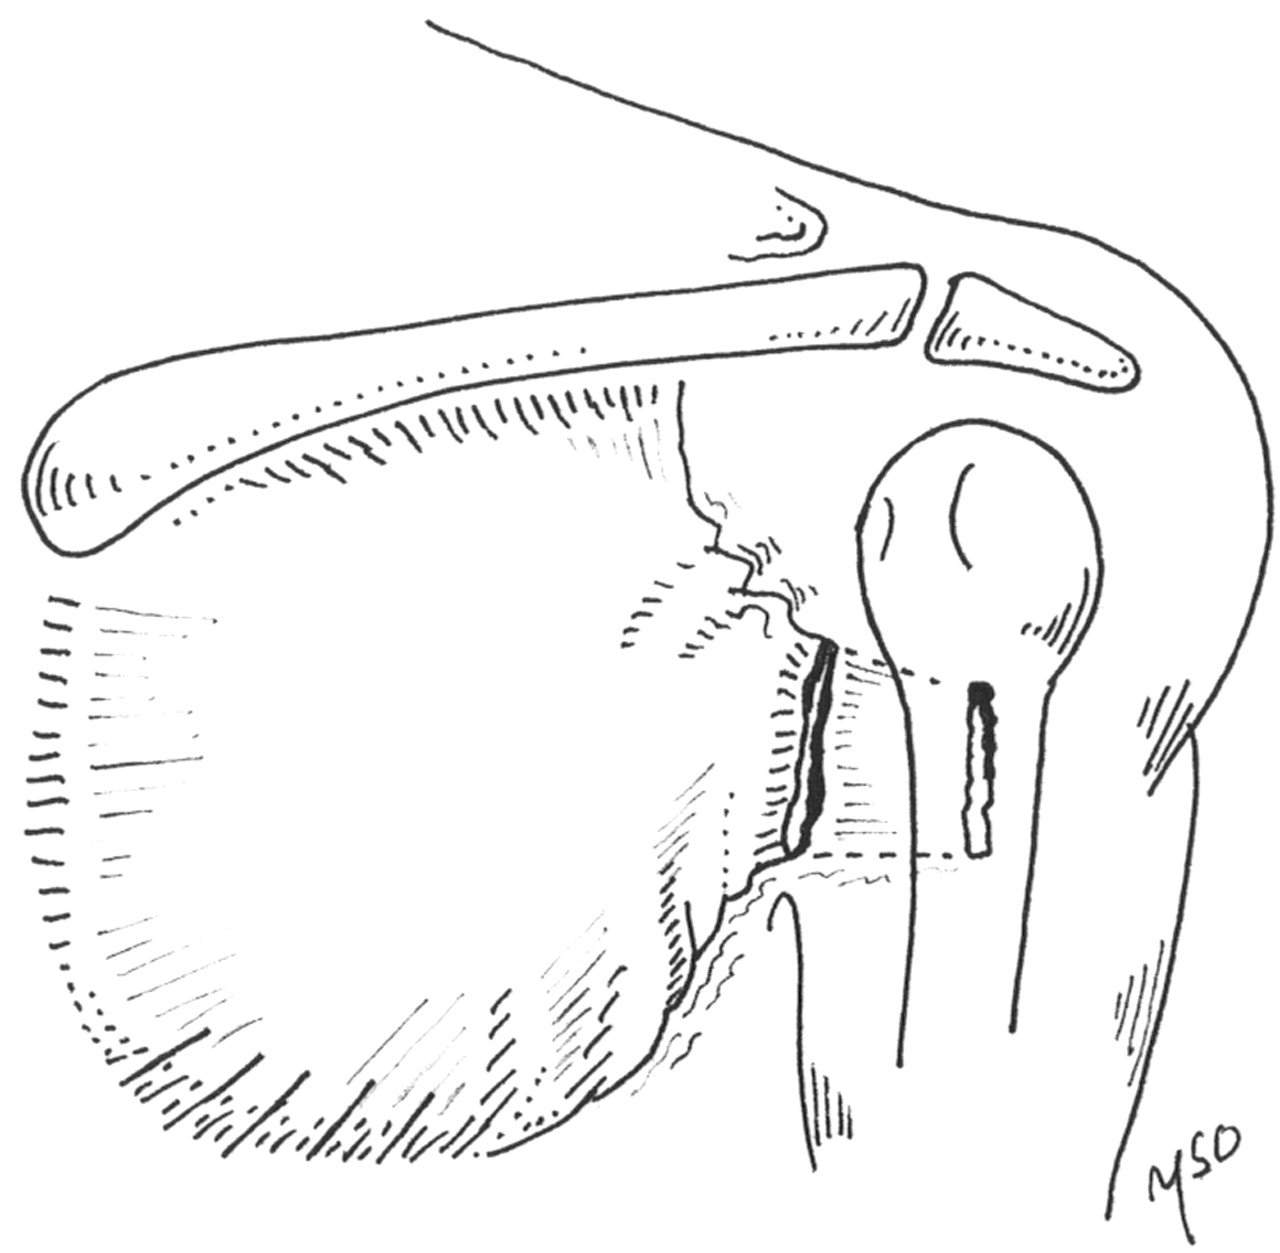

This is what has happened:

An MRI scan of his left pectoralis major muscle was performed. It confirmed a tear of the left pectoralis major muscle. The muscle and tendon usually rips off the insertion into the humerus bone. In his case, the tendon was still attached to the humerus bone but the muscle was torn in the junction between muscle and tendon (musculotendinous junction).